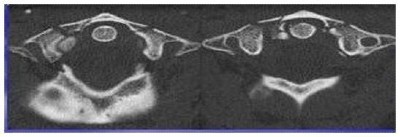

Fracture de Jefferson au niveau de l’arc antérieur C1 (première vertèbre) et élargissement du canal rachidien secondaire à la fracture de l’arc antérieur de C1.

Les radiographies peuvent détecter plusieurs fractures cervicales, telle que la fracture de Jefferson au niveau de la deuxième vertèbre. Ce type de fracture crée une ouverture de l’anneau de la première vertèbre et, en conséquence, un élargissement du canal rachidien (conduit à l’intérieur de la moelle épinière). Il est possible de voir une entorse grave des deux premières vertèbres. Ce trauma est souvent lié à une hyperflexion du cou, ce qui donne lieu à une lésion du ligament transverse empêchant un frein postérieur. Une partie de la première vertèbre cervicale se déplace alors vers l’arrière et comprime le canal spinal. Il est donc possible de voir, sur une radio de profil, le déplacement de l’arc antérieur de C1 et la face antérieure de l’odontoïde.